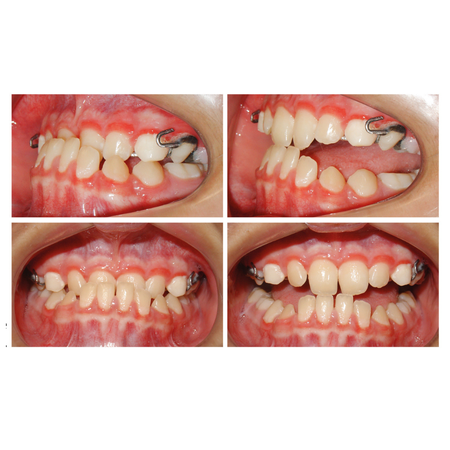

INTRODUÇÃO: O gerenciamento dos espaços das agenesias dentárias é frequentemente relatado como um desafio adicional para o tratamento ortodôntico e, quando associado à má oclusão esquelética, torna o tratamento mais complexo. OBJETIVO: Neste relato de caso, objetivou-se apresentar um tratamento ortopédico seguido de tratamento ortodôntico compensatório de um paciente Classe III esquelética severa com agenesia dentária múltipla. RELATO DE CASO: Paciente do sexo masculino, com 14 anos de idade, teve um plano de tratamento atípico, inicialmente tratado com máscara facial...

INTRODUÇÃO: O gerenciamento dos espaços das agenesias dentárias é frequentemente relatado como um desafio adicional para o tratamento ortodôntico e, quando associado à má oclusão esquelética, torna o tratamento mais complexo. OBJETIVO: Neste relato de caso, objetivou-se apresentar um tratamento ortopédico seguido de tratamento ortodôntico compensatório de um paciente Classe III esquelética severa com agenesia dentária múltipla. RELATO DE CASO: Paciente do sexo masculino, com...

INTRODUCTION: Space management of tooth agenesis is often reported as an additional challenge for orthodontic treatment and, when associated with skeletal malocclusion, makes the treatment more complex. OBJECTIVE: The objective of this case report was to present an orthopedic treatment followed by comprehensive orthodontic treatment of a severe skeletal Class III patient with multiple tooth agenesis. CASE REPORT: A 14-year-old male had an atypical treatment plan, starting with facemask...